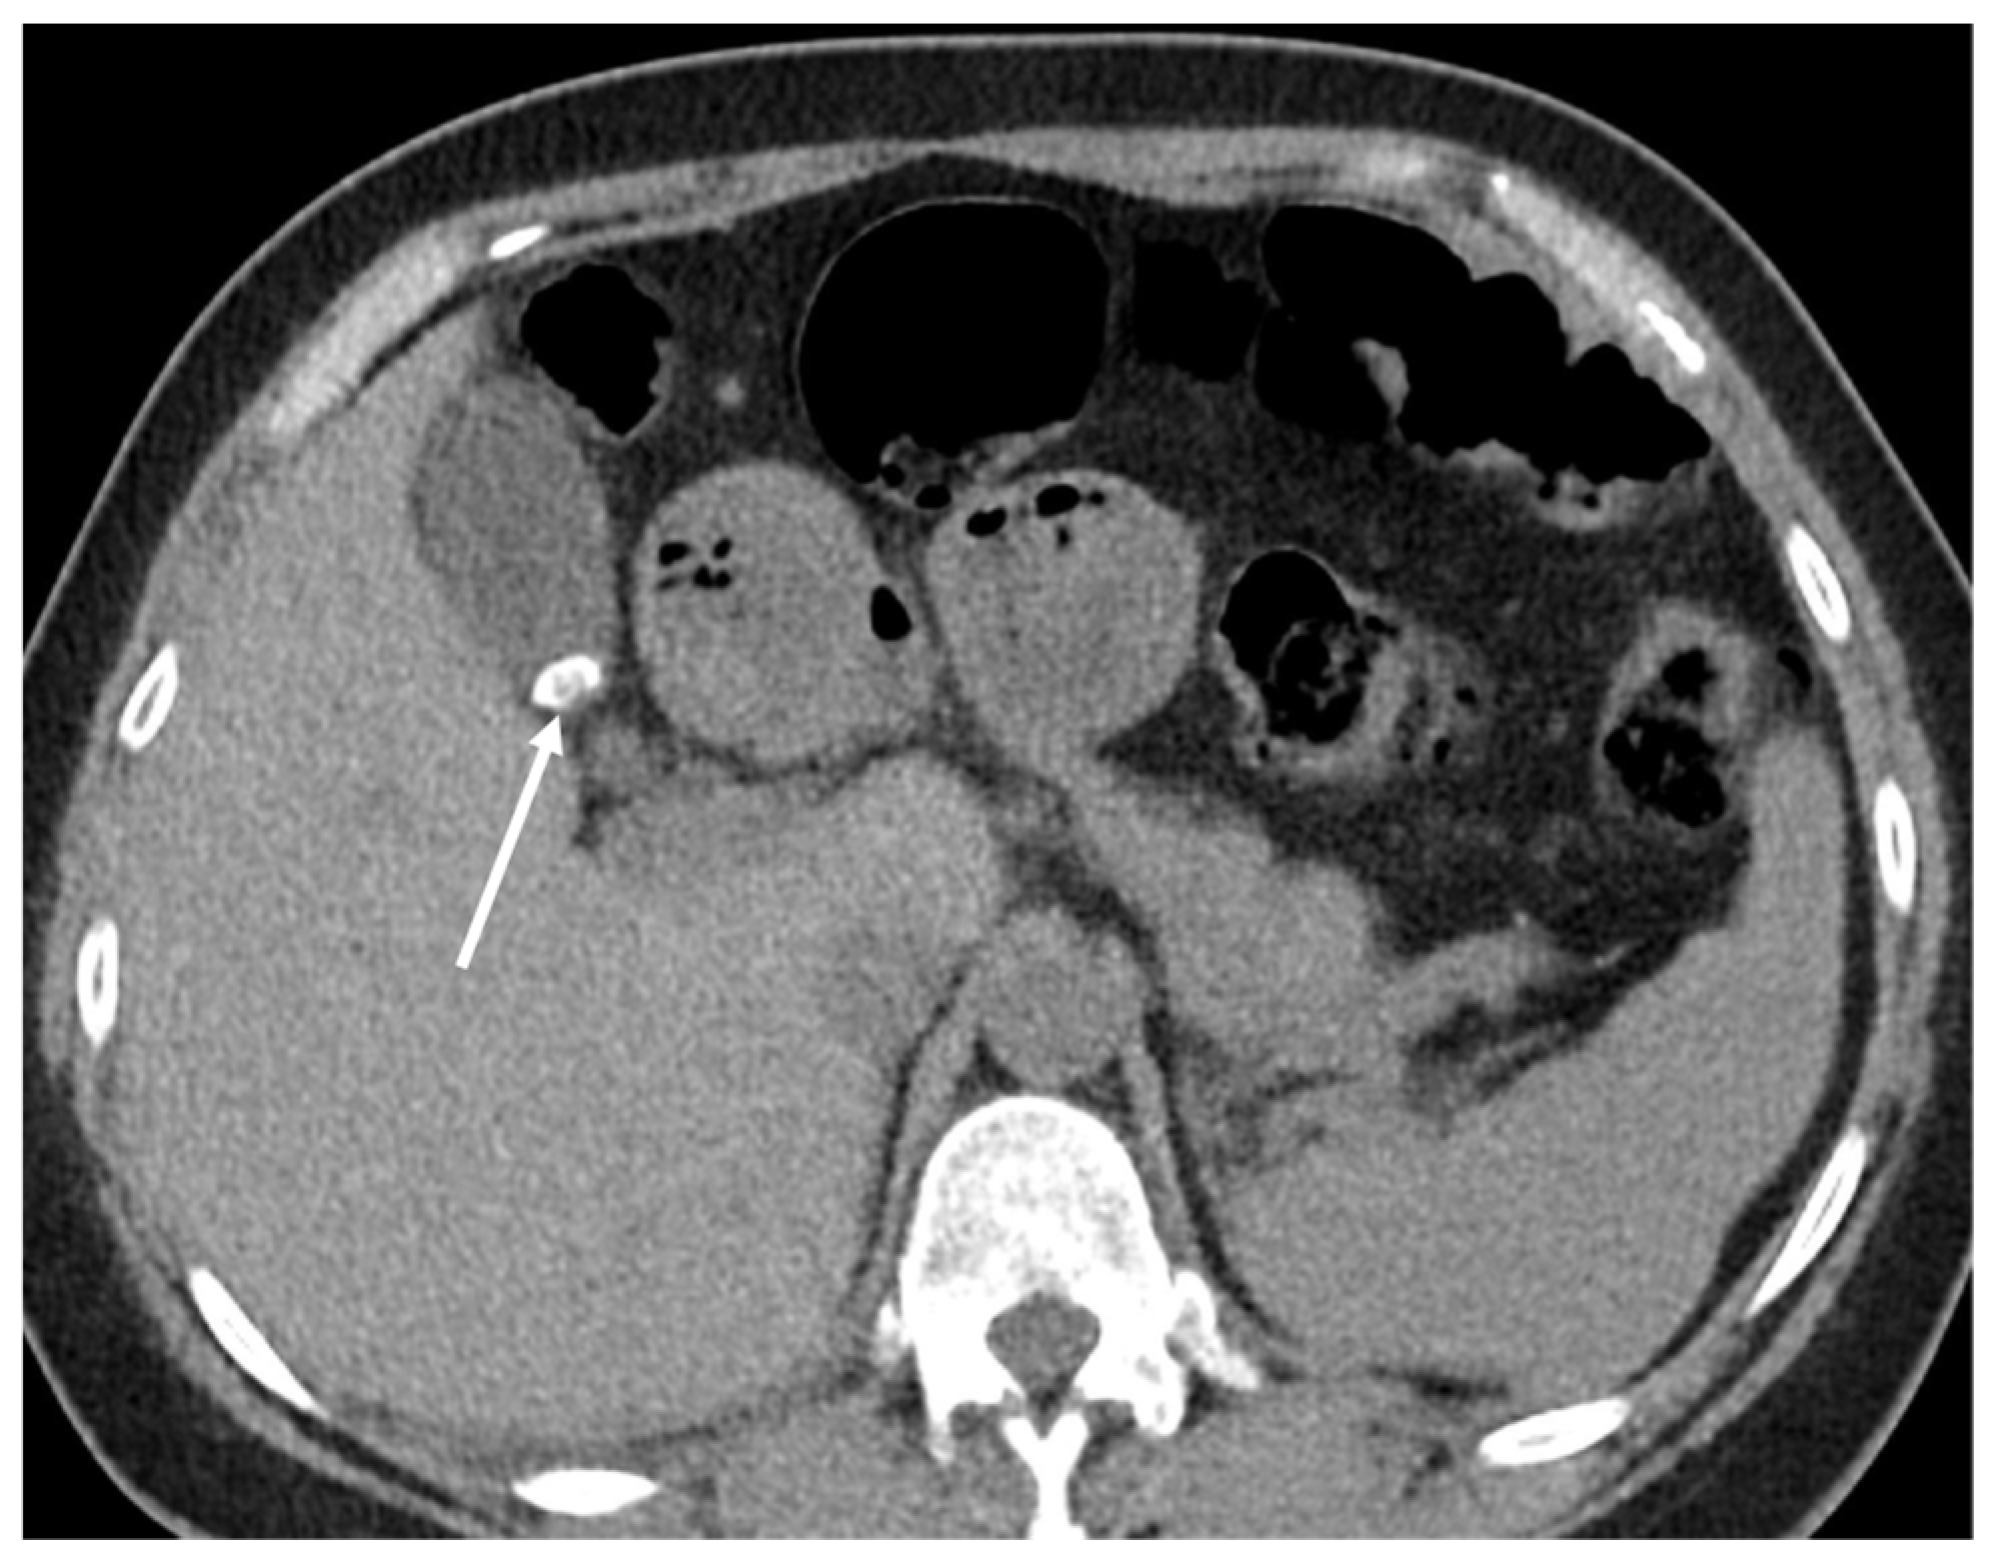

5.3.2. Adrenal Gland